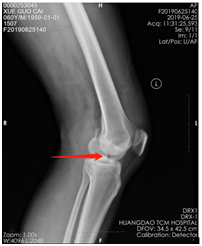

薛大叔左膝外侧有(以腓骨小头为中心)约10cmX15cm皮肤挫伤,其中间约5cmX8cm皮肤色紫,血运差;膝关节内上侧有约6cmX25cm皮肤挫伤,血运不满意 。医生为其进行了详细检查,确诊为左股骨内后髁骨折(Hoffa骨折)、左腓骨小头骨折、左膝内侧半月板损伤、左下肢挫裂伤 。

术前CT片